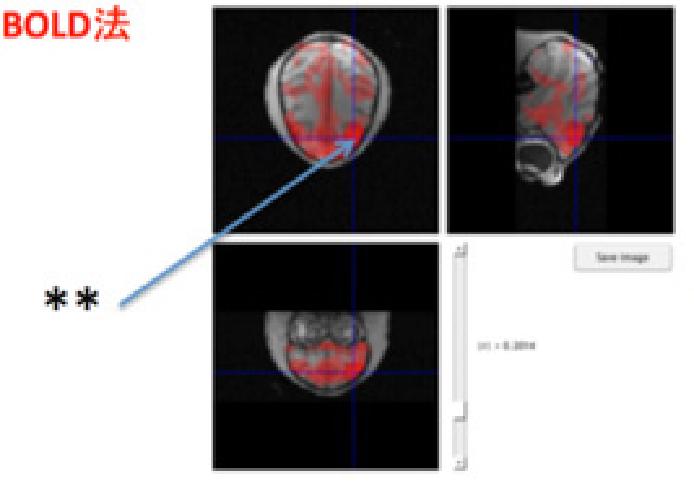

rs-fMRI(resting state fMRI)​

安静時における脳の神経活動を測定する技術です。脳領域間における機能的結合や安静時の神経活動(デフォルトモードネットワークなど)の観察に用いられています。

神経科学や心理学、臨床医学など多くの研究に利用されています。​

安静時における脳領域間の機能的結合を評価しています。(Functional Connectivity)

​アカゲザルの特定の脳領域(**)に対して相関がある脳領域を評価しています。​